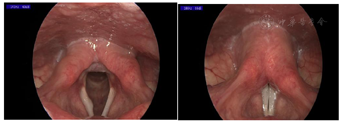

术后第1天复查频闪喉镜:可见右侧囊肿消失,声带边缘光滑,右侧声带黏膜波稍下降,未见明显肿物残留,轻度充血肿胀。喉后部充血,黏膜轻度增生,发音时,可见声门闭合见一梭形缝隙(图3A、图3F)。

术后20 d,患者声嘶无改善,复查频闪喉镜检查见手术创面愈合良好,右侧声带下唇处见一肉芽,呈淡红色,大小约3 mm×3 mm,表面光滑,局部黏膜波下降,发音时声门闭合见一梭形缝隙。双侧声带内收及外展运动正常(图3B、图3G)。

治疗后15 d,患者诉声嘶、发声困难较前改善,复查喉镜见右侧声带下唇处见一肉芽较前缩小(图3C、图3H)。继续予雷贝拉唑20 mg bid口服2周。

治疗后28 d复查频闪喉镜:右侧声带肉芽完全消失(图3D、图3I)。考虑到患者在发音时声门上仍有轻度挤压征、声门闭合不全的情况,评估后给予共鸣嗓音疗法进行嗓音训练,以优化声带的闭合程度、减轻声门上挤压征,提高音量、改善嗓音。

治疗后3分月复查,患者右侧声带边缘光滑,未见肉芽复发,发音时,声门闭合良好,黏膜波正常,嗓音功能基本正常(图3E、图3J)。